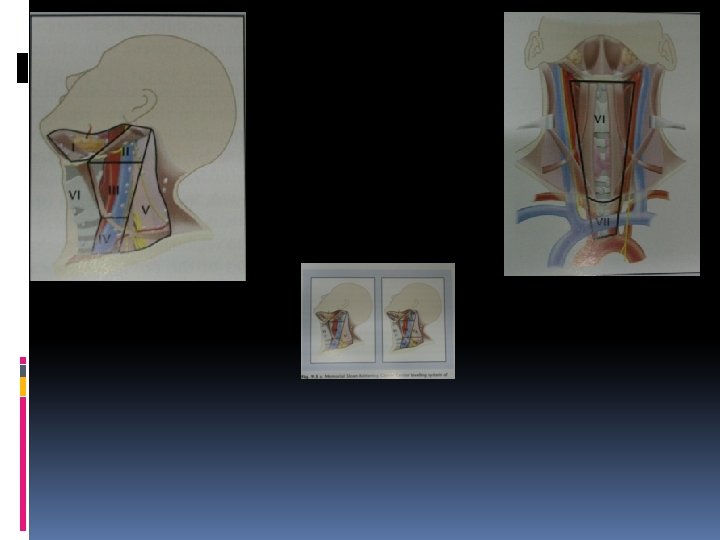

Lymphatics of oral cavity Level 1 – submental and submandibular groups Level 2 – upper deep cervical groups along the upper 1/3 rd of I. J. V. Level 3 – mid-deep cervical lymphnodes along the middle 1/3 rd of I. J. V. extending upto superior belly of omohyoid muscle Level 4 – the lower deep cervical lymphnodes along I. J. V. from superior belly of omohyoid Level 5 – Lymphnodes in the postrior triangle of the neck mainly along the spinal acc. n

IN CASE OF EXTENSIVELY INVOLVED LYMPH NODES NECK DISSECTION IS INDICATED LYMPH NODES IN THE NECK ARE CLASSIFIED AS LEVELS I TO VII LEVEL IA SUBMENTAL GROUP LEVEL IB SUBMANDIBULAR GROUP LEVEL II UPPER JUGULAR GROUP LEVEL III MID-JUGULAR GROUP LEVEL IV LOWER JUGULAR GROUP LEVEL V POSTERIOR TRIANGLE GROUP LEVEL VI CENTRAL COMPARTMENT GROUP LEVEL VII SUPERIOR MEDIASTINAL GROUP